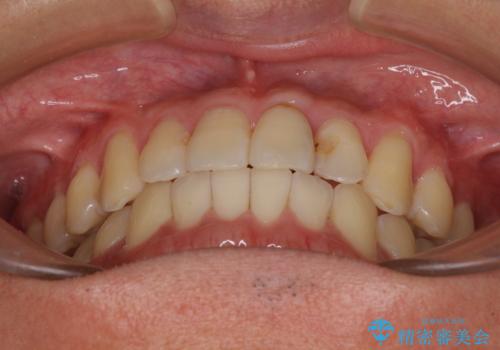

気になる前歯のデコボコをインビザラインで解消

- 前歯のデコボコを気にして来院された患者様です。

主に下顎歯列全体の後方移動とIPR(歯と歯の間を削る)によってデコボコが解消するように設計し、インビザラインにより治療を行うこととしました。

インビザライン矯正特有の、治療後半で前歯のみが強く接触する症状が発現し、咬み合わせ改善に期間を要することとなりました。